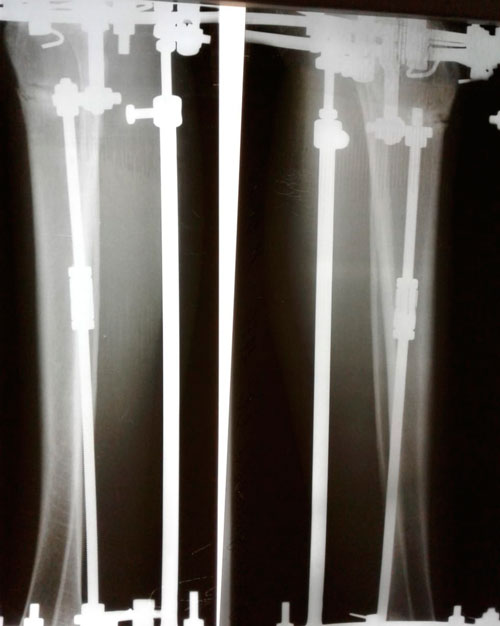

Рентген в 60 дней.

"Сращение идёт отлично! Ждем на снятие аппаратов, через 2 недели."